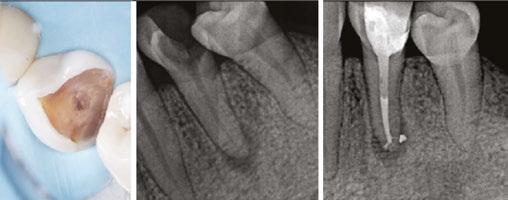

Necrotic case — Pretreatment (left) and post GentleWave treatment (right)

With the enhanced CleanFlow Procedure Instrument, I am able to shave about 5 to 7 minutes off each root canal procedure I perform, as compared to the prior procedure instrument.

CleanFlow Technology enables the inside of the tooth to be cleaned from the outside. When I first tried it, I was a bit skeptical that a cleaning action generated outside the tooth could be as effective as when the cleaning action is produced in the pulp chamber. Now, I am highly confident in it.

As endodontists, we know that patients don’t want to have to come to our offices for treatment more than once. With the GentleWave System, single-visit procedures are more likely than ever before. Additionally, most of my patients have little to no postoperative issues with the Gen tleWave System with CleanFlow Technology. Not only is this incredible for my patients, but it also frees up time and resources for my staff.